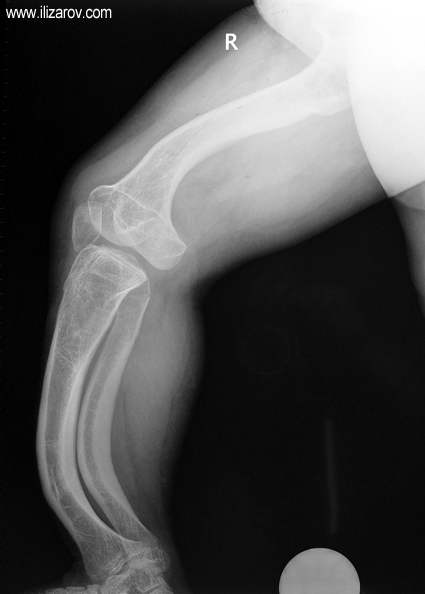

In hypophosohatemic rickets, abnormal bone findings become evident after 1 year of age; there are short stature and deformities around the knee (bilateral genu valgum or varum, tibial torsion, deformity at tibia and femur, ‘windswept’ deformity).

Because the deformity caused by hypophosphatemic rickets is very close to the growth plate, a significant deformity and malalignment occurs. For that reason, more than one deformity centers (CORA) are found at preoperative evaluation, and osteotomy at more than one level is required to correct the deformity. The most frequently used methods to correct the deformity are acute or gradual deformity correction using the Ilizarov method or unilateral external fixator. In the ‘fixator assisted nailing’ technique, which is applied in our department, the deformity is corrected in an acute fashion with the help of an external fixator, and the extremity is stabilized by an intramedullaru nail. The external fixator is removed before the end of the surgery if no gradual lengthening is planned postoperatively. If lengthening (over nail) is planned, the fixator is removed after the completion of the lengthening procedure. As a result, the risk of pin tract infection is eliminated, correction loss and relapsing of the deformity (which are important problems in the treatment of hypophosphatemic rickets) are avoided, eary motion and full weight bearing are allowed, and comfortability of the patient is improved because the duration with external fixator is decreased.

Case 2